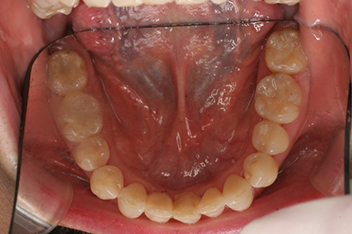

非抜歯のケース / 24歳(治療期間2年3か月)

部分矯正

わずかな重なりや、すき間など気になる部位だけを部分的な装置で改善します。

63歳(治療期間6か月)

下の前歯を一本抜歯して、部分矯正にて治療しました。見た目はもちろん、歯磨きがしやすくなるという大きなメリットもあります。